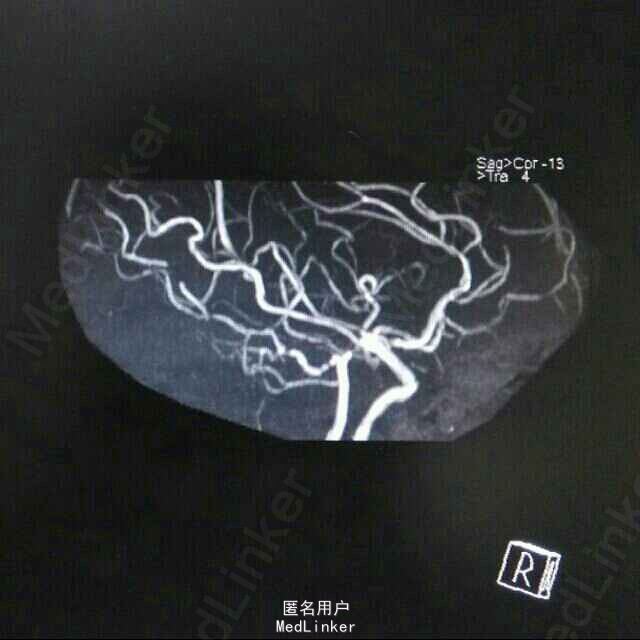

查体:BP 136/84mmHg,抬腿右下肢较左侧差,余无明显异常。 辅检:6-8 D-D 1.87,FIB 7.15,ALT 38,AST 46,GGT 37,LDL-C 4.38,铁蛋白 320,CRP 96.7,ESR 70,尿酮体1+ 6-15 PLT 469,ALT 53,GGT 50,ESR 38,D-D 0.59 血糖监测:早餐后高 彩超多普勒:升主动脉较宽,左室舒张功能减低;双侧颈动脉粥样硬化斑形成。 经颅多普勒:双侧颈内动脉、颈外动脉、左侧颈总动脉血流速度减慢;左侧锁骨下动脉、右侧大脑中动脉、大脑前动脉、左侧颈内动脉虹吸部管腔呈收缩状态;左侧颈内动脉虹吸部管腔重度狭窄;各检查动脉管腔应硬化。 头部MR、脑动脉造影MRA:脑干右侧11*12mm梗塞灶;腔隙性脑梗塞;脑萎缩;双侧额部顶部硬膜下积液;左侧椎动脉起始段及椎动脉-基底动脉汇合段管腔中度狭窄,双侧颈总、颈内外动脉、双侧大脑前中后动脉多发中-重度狭窄,动脉粥样硬化表现。

诊断:脑梗塞;高血压病3级 极高危;糖尿病 2型;动脉粥样硬化;高脂血症;慢性胃炎 治疗:依达拉奉、马来酸桂哌齐特、丹森川穹嗪注射,小牛血清去蛋白注射液;硝苯地平缓释片;阿司匹林肠溶片;阿托伐他丁钙片;阿卡波糖片。